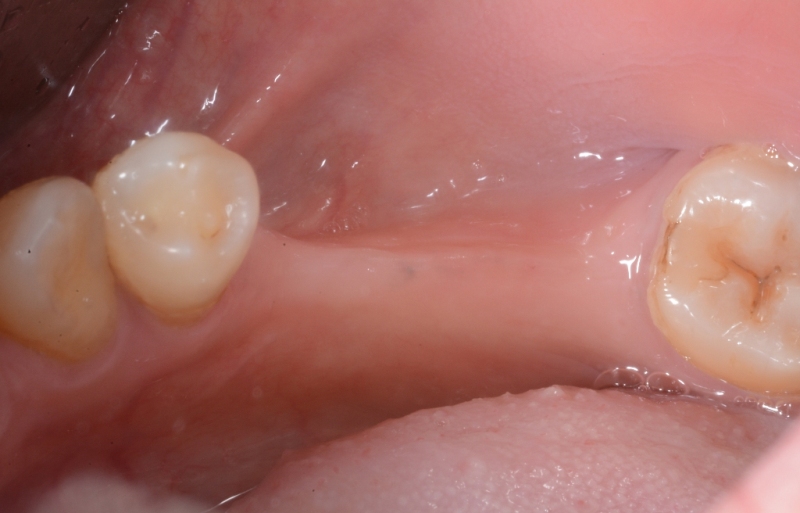

牙肉重建術案例

案例2

牙肉重建術前

牙肉重建術後